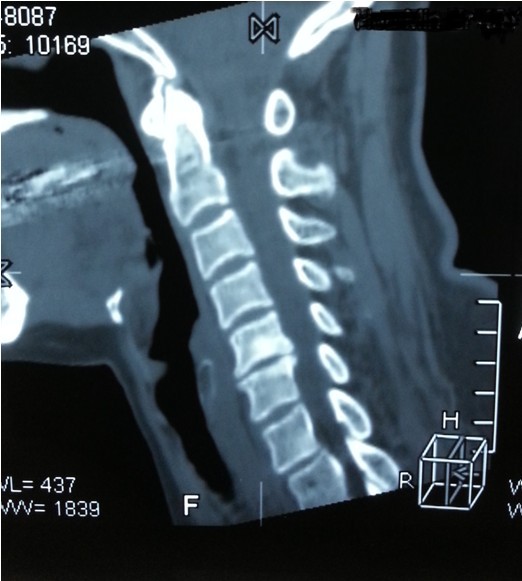

我院副院長(zhǎng)兼脊柱科主任劉志安詢問(wèn)病史后,詳細(xì)查體并攝片,發(fā)現(xiàn)患者是頸椎間盤(pán)突出,骨質(zhì)增生,壓迫頸椎神經(jīng),引起頸肩部酸脹難忍,雙手麻木乏力,若不盡快處理,癥狀將進(jìn)一步加重,建議患者盡早手術(shù)治療,否則將喪失最后的手術(shù)時(shí)機(jī),有致癱瘓的可能。

一開(kāi)始,處于對(duì)手術(shù)以及住院費(fèi)用的恐懼,患者要求保守治療,可是如此嚴(yán)重的椎間盤(pán)突出,保守治療根本無(wú)法解除對(duì)頸椎的神經(jīng)的壓迫。劉副院長(zhǎng)詳細(xì)向患者講述其病情起因,發(fā)展,變化,轉(zhuǎn)歸,并表示,患者頸椎手術(shù)總費(fèi)用預(yù)計(jì)在5萬(wàn)以內(nèi),報(bào)銷(xiāo)后自費(fèi)約4萬(wàn)左右,考慮患者家庭困難,可聯(lián)系紅十字基金會(huì)予以適當(dāng)?shù)难a(bǔ)貼,考慮再三,最終患者選擇到我院手術(shù)治療。手術(shù)結(jié)束后,患者慢慢開(kāi)始恢復(fù),頸肩部酸脹不適癥狀消失,雙手麻木乏力癥狀較術(shù)前大為緩解,兩周后出院,患者及家屬對(duì)手術(shù)治療效果,醫(yī)生護(hù)士服務(wù)態(tài)度,以及花了3萬(wàn)元就解決困擾多年的疾病均表示非常滿意。